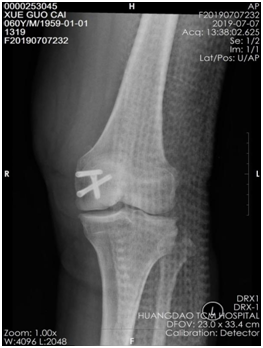

薛大叔左膝外侧有(以腓骨小头为中心)约10cmX15cm皮肤挫伤,其中间约5cmX8cm皮肤色紫,血运差;膝关节内上侧有约6cmX25cm皮肤挫伤,血运不满意 。医生为其进行了详细检查,确诊为左股骨内后髁骨折(Hoffa骨折)、左腓骨小头骨折、左膝内侧半月板损伤、左下肢挫裂伤 。

术前CT片